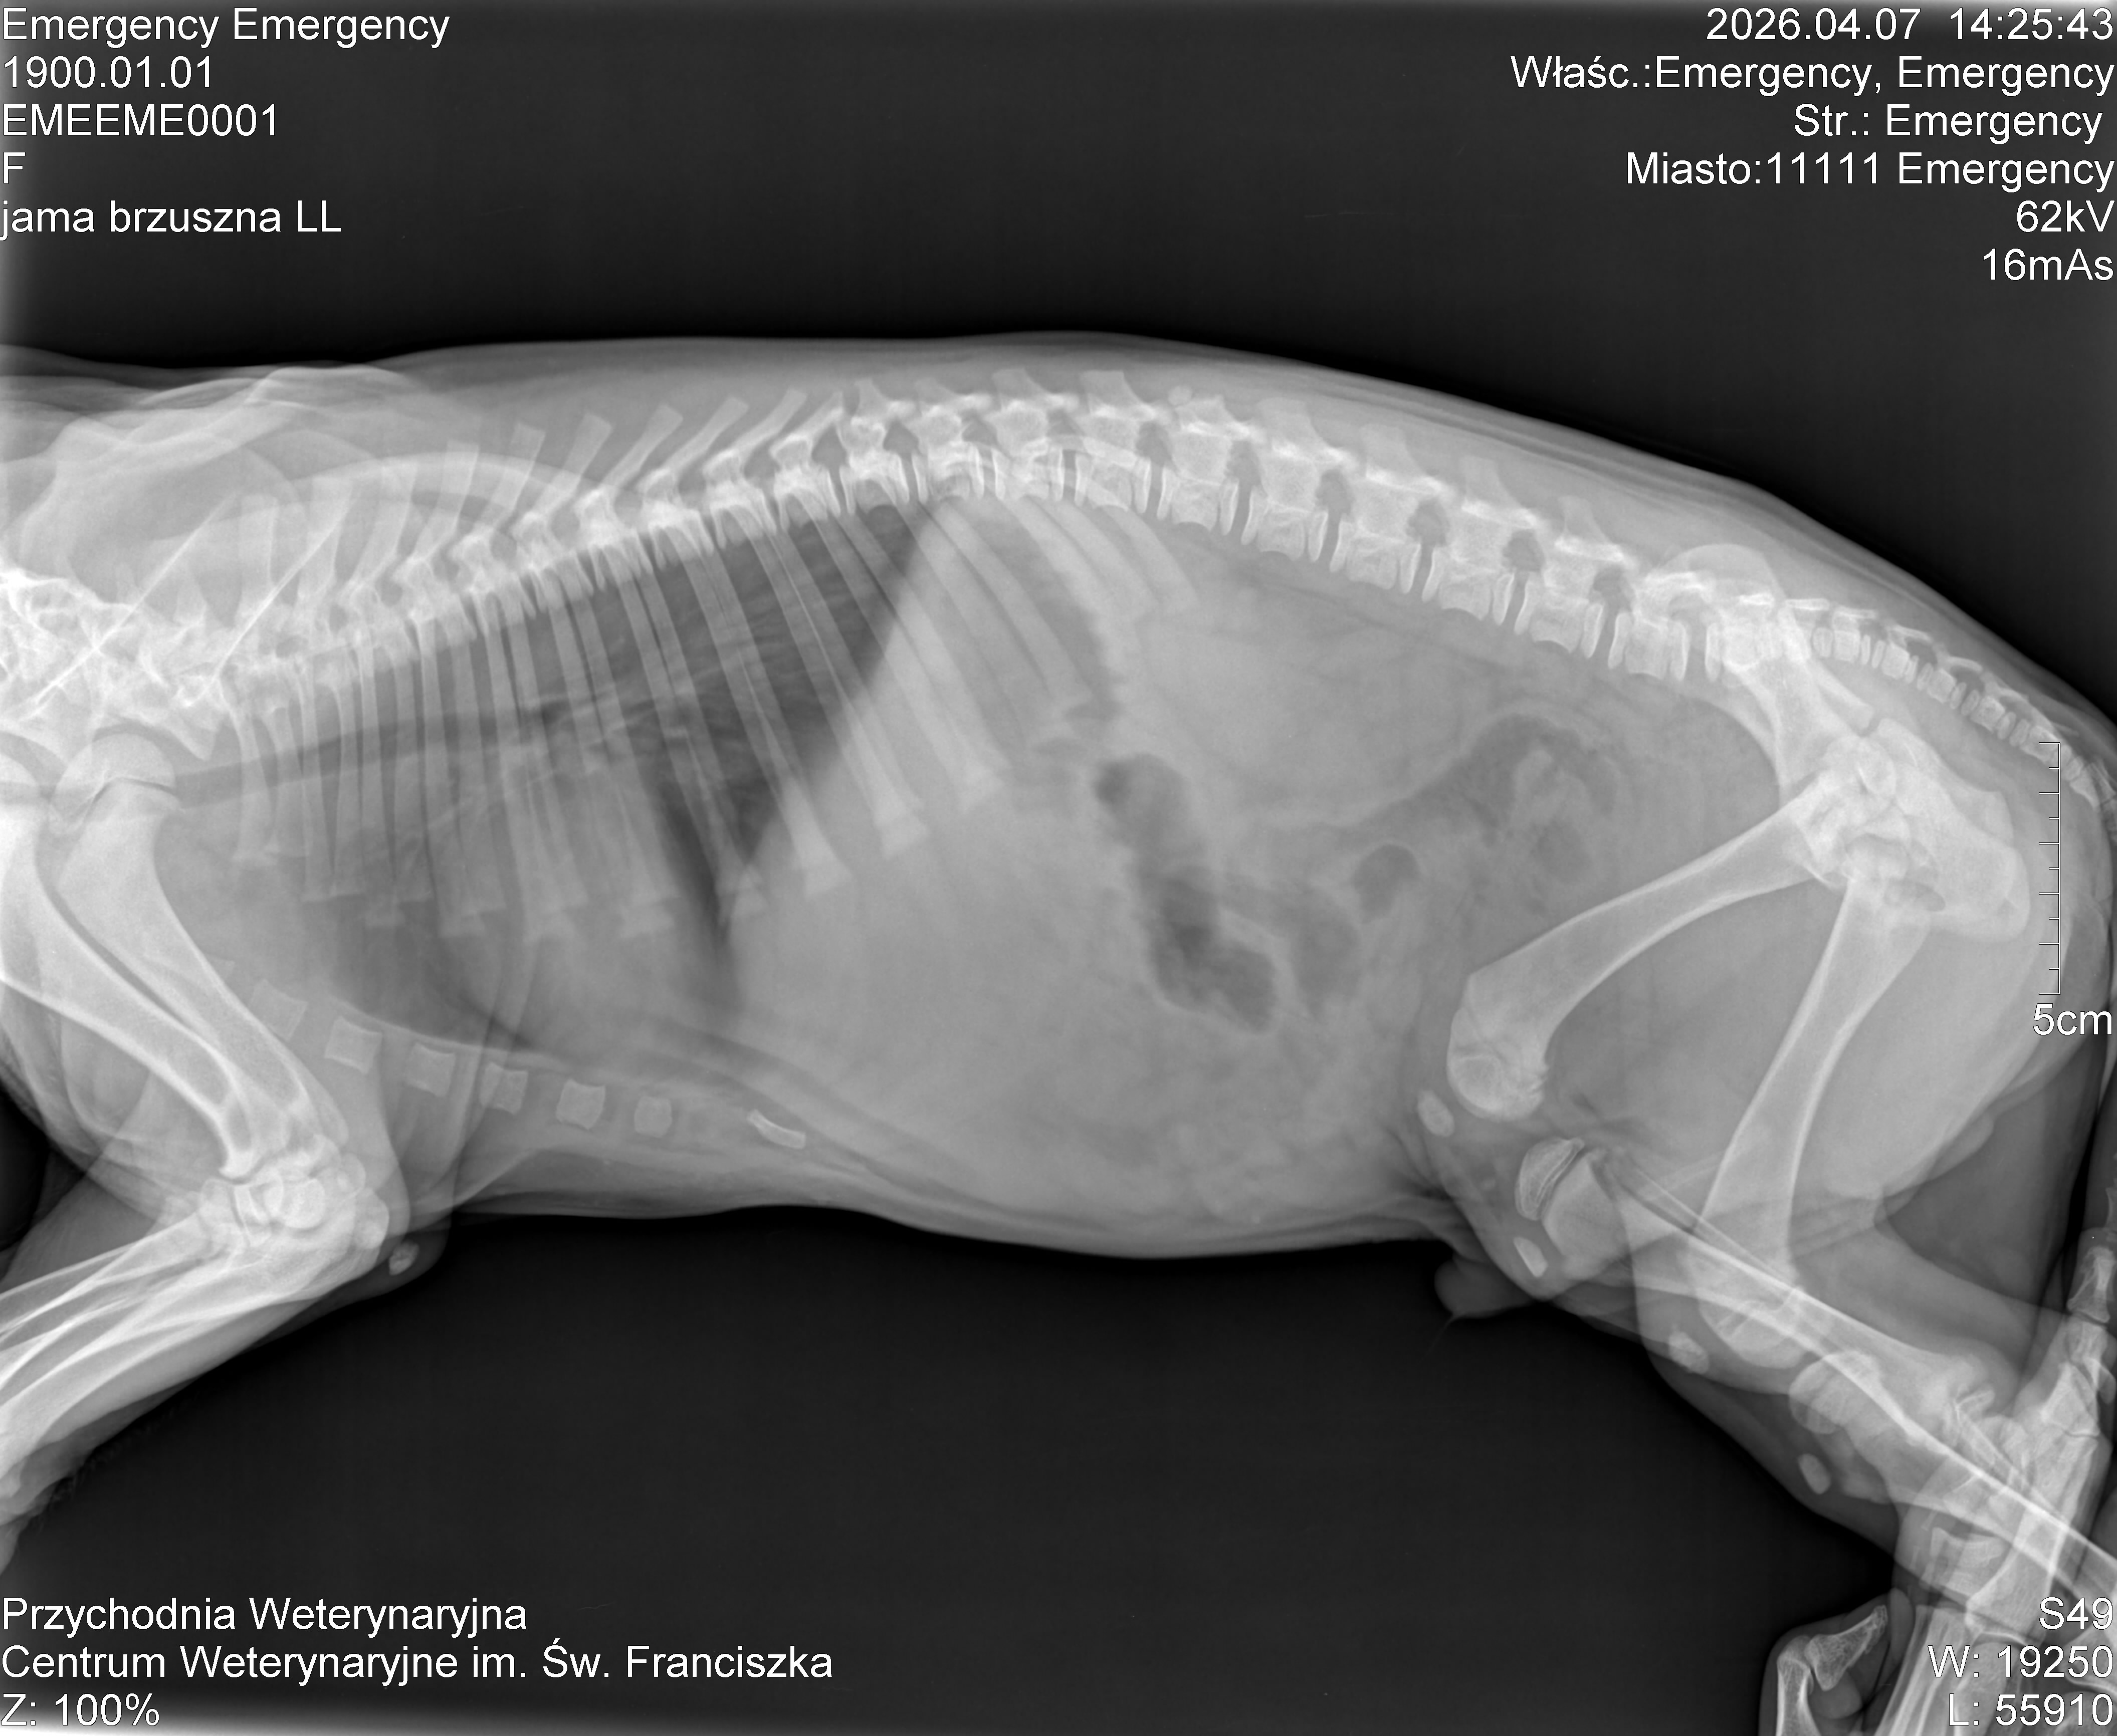

31.03.2026 przybyły na nasz pokład maluchy.

Tata w typie cane corso, mama mix molosów.

Pieski będą duże.